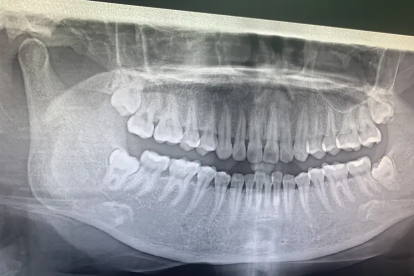

反复发炎或阻生的智齿建议口腔外科手术拔除。术前需拍摄口腔全景片评估智齿位置,术中采用局部麻醉,术后24小时内避免漱口和剧烈运动。拔牙创口一般3-5天初步愈合,完全恢复需1-2个月。